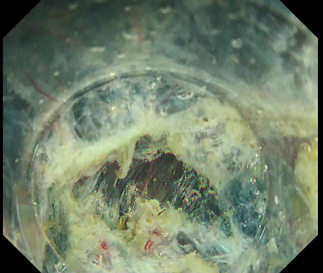

In this case, it would also be acceptable to use a traction device at the initial stage. We will show an example using traction in another case: an LST that appears to enter the ileocecal valve. Although the terminal ileum side of the lesion is difficult to see, applying traction after incision makes it easier to identify the resection line. Applying a second traction device in a different direction can further facilitate resection (Fig. 12).

Fig. 12

Fig. 13

Be careful when using traction. Traction in the wrong direction will not yield the expected result, and excessive traction can tear the mucosal flap. In addition, the muscular layer is often pulled by traction, which can lead to perforation if the dissection line is mistaken. Therefore, it is necessary to pay close attention to the resection line (Fig. 13).